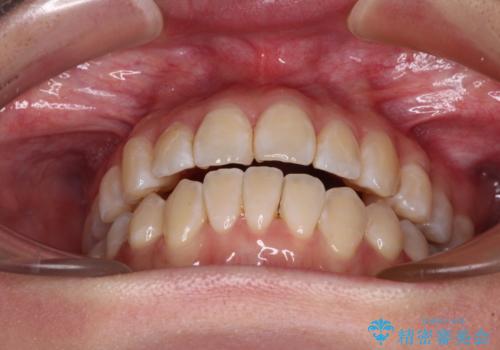

外に飛び出して磨きにくい奥歯と上下前歯の隙間 インビザラインによる矯正治療

- 上下前歯の隙間と、外側を向いていて歯磨きのしにくい奥歯を気にして来院された患者様です。

下顎前歯が1本欠損しており、上下アーチはアンバランスとなりますが、インビザラインを用いて上下の隙間を改善しながら歯列を整えることとしました。

下顎前歯の1本欠損により左右の咬合が不安定となり、治療経過で噛みにくい状態が続きましたが、最終的には違和感なく噛めるようになりました。